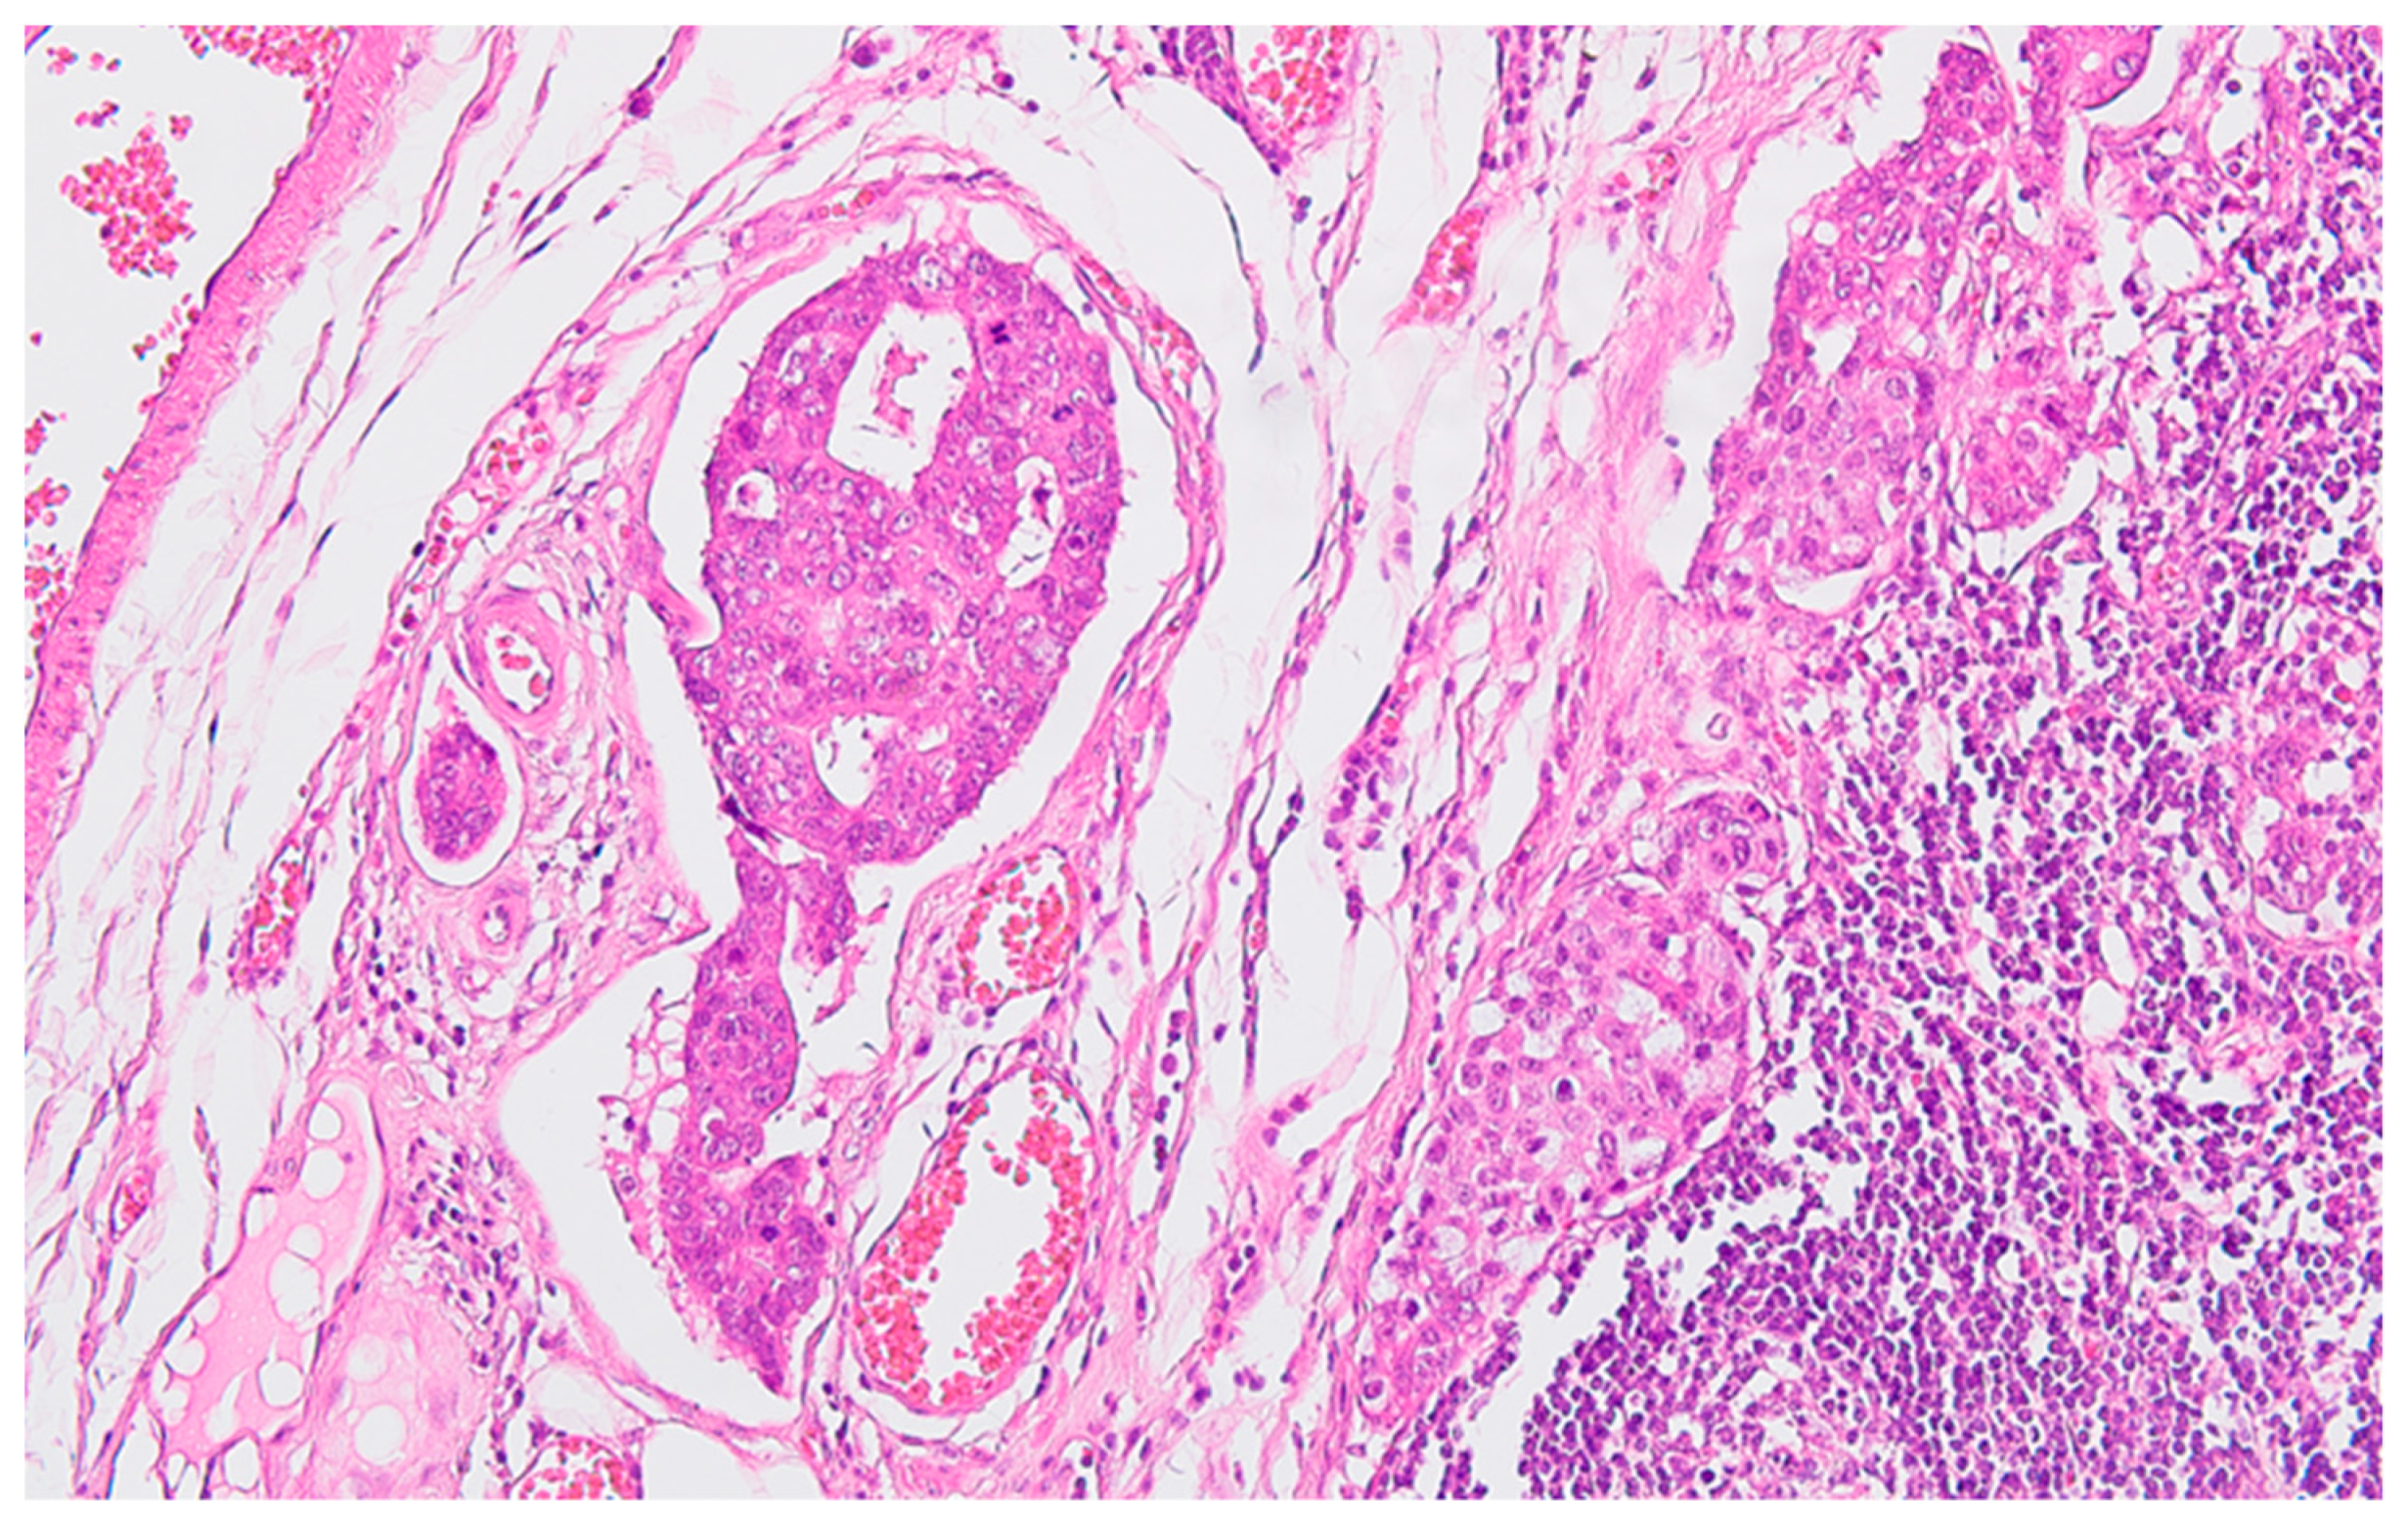

Figure 3. Regional lymph node metastasis of the colon carcinoma, with adenocarcinoma pattern in the afferent lymphatics and subcapsular sinuses, HE x200.

Serial sections of the ascending colon tumor reveal massive infiltration of a diffuse, mucinous carcinoma, with predominantly intracellular secretion of mucin ("signet ring" cells); some isolated aspects of mucinous tubular adenocarcinoma are also observed. The tumor is ulcerated on the surface, extensively invades the submucosa (Figure 1), and dissociates the muscular layer (muscularis propria), being found massively in the subserosa (Figure 2), with perforation of the visceral peritoneum: tumor cells in ink or less than 1 mm from the inked serosa (pT4a); numerous lymphatic tumor emboli, frequent aspects of perineural invasion. Of 26 lymph nodes, 24 show massive carcinomatous metastases (adenocarcinoma type, Figure 3) - pN2b.